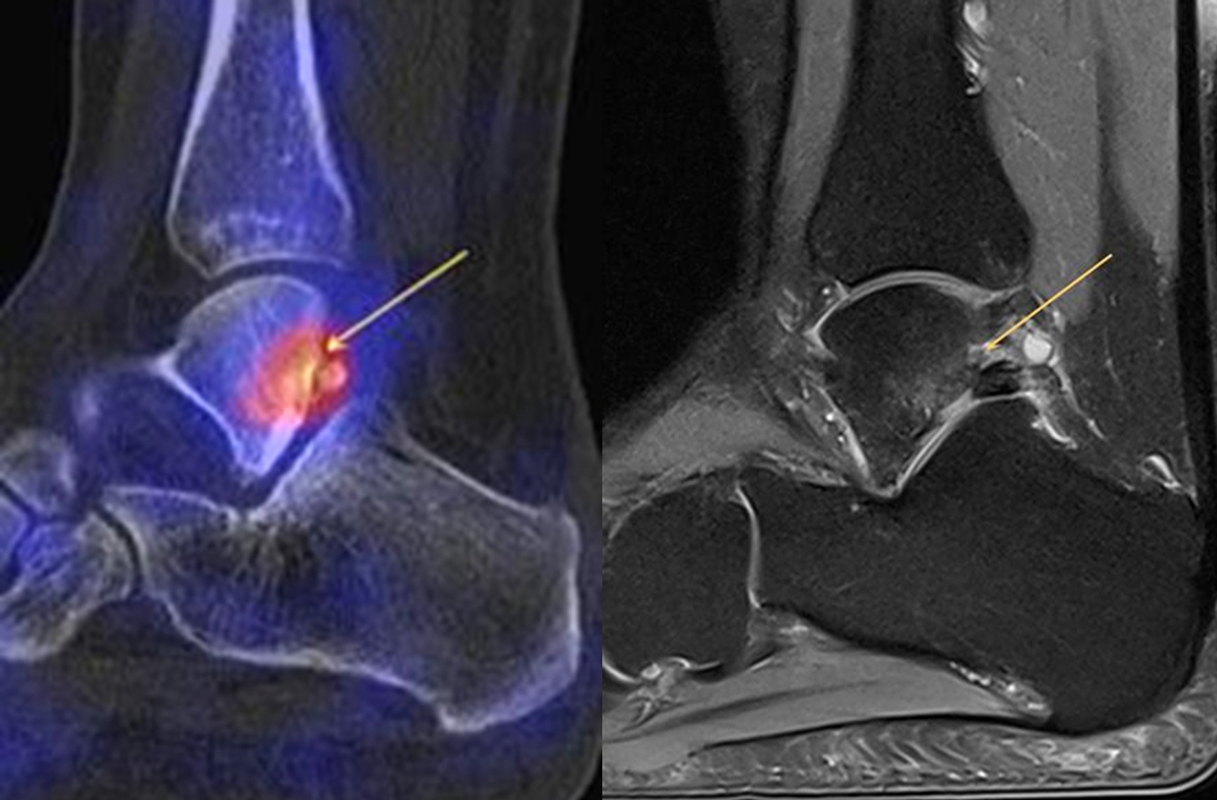

Abbildung 8.1. a bis f.: Patient mit Z. n. OSG-Distorsion vor 8 Monaten und konservativer Therapie. Anhaltende Schmerzen im Bereich des linken Innenknöchels. Im MRT bestand der Verdacht auf eine symptomatische kleine osteochondrale Läsion im medialen linken Talus (Abbildung 8.1. a und c). Zur weiteren Klärung erfolgte eine SPECT/CT 30 Tage später, welche jedoch im Gegensatz zur MRT eine fokale Mehrspeicherung an der tibialen Insertion des Deltabandes nachwies. Die Tatsache, dass die SPECT/CT spezifischer als die MRT symptomatische Bandläsionen detektieren kann wird untenstehend ausführlich thematisiert.

Abbildung 8.2. zeigt den Fall eines Patienten mit Verdacht auf ein knöchernes posteriores Impingement. Es bestanden Beschwerden dorsal bei Plantarflexion und ein Z. n. Distorsion des linken OSG vor 2,5 Jahren. Im MRT 2 Monate vor der SPECT/CT keine wegweisenden Befunde. Im SPECT/CT eindeutige fokal deutliche Mehrspeicherung im Bereich des Processus posterior tali.

Abbildung 8.3.a bis d demonstrieren Bilder einer Patientin mit Z. n. Arthrodese des linken OSG vor 6 Jahren. Das MRT ist bei ausgedehnten Metallartefakten nur bedingt aussagekräftig und weist nicht auf die auffälligen Befunde im SPECT/CT hin. Es bestehen sowohl fokale Stressreaktionen im Bereich eines Os trigonum und lateral im USG.

Abbildung 8.4.a bis d: Bilder einer Patientin mit chronischen Schmerzen im lateralen unteren Sprunggelenk links. Im MRT V. a. akzessorisches Knochenelement. Anamnestisch Beschwerden im Bereich des linken Sprunggelenkes seit 5 Monaten. Zuvor intensive sportliche Betätigung. Unter anderem tägliche atypische Belastung beider Füße durch Hinknien im Rahmen der Tätigkeit als Erzieherin. Diese Patientin hat nebenbefundlich bilaterale Akzessoria bzw. einen beiderseits angelegten Talus secundarius, der linksseitig jedoch nicht für die Symptomatik verantwortlich ist (die Bilder davon werden in Abbildung 3.5. gezeigt). Verantwortlich für die Symptomatik ist ein links posterolateral am Talus atypisches Knochenelement in einer Mulde mit engem Bezug zum unteren Sprunggelenk, DD atypisches laterales Os trigonum oder DD atypische Osteochondrosis dissecans. Die MRT konnte nicht differenzieren, wo die Schmerzursache genau lag. Im SPECT/CT (Abbildung 8.4.b und d) eindeutig fokale Mehrspeicherung im Bereich des atypischen Knochenelementes. Intraoperativ bestand der Aspekt einer Osteochondrosis dissecans.